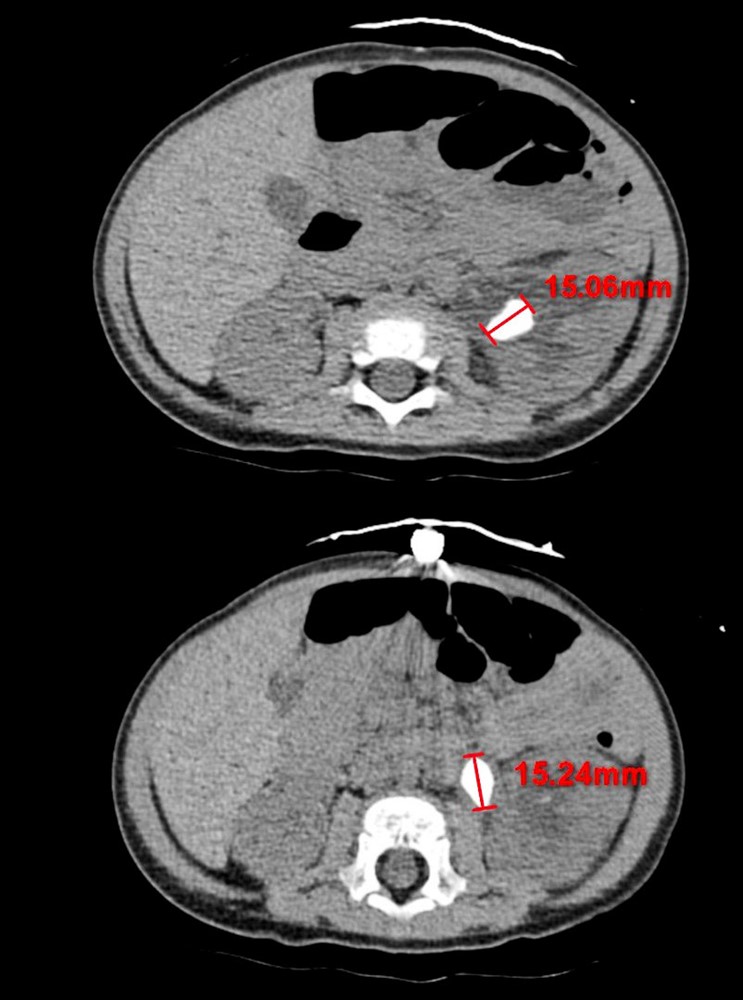

電腦斷層不同切面顯示,十一個月大的嬰孩腎臟有兩顆約一點五公分大的結石。圖/花蓮慈院提供

十一個月大的男嬰體內居然長出兩顆約一點五公分大的腎結石並造成急性腎臟發炎!花蓮慈濟醫院兒科部小兒腎臟科主任陳明群醫師指出,文獻資料也極少有年紀這麼小的孩童腎結石的紀錄。花蓮慈院小兒部與泌尿部團隊攜手合作,先利用藥物控制男嬰的感染情況,再使用全院最小尺寸的腎臟鏡,以「經皮腎鏡取石手術」將腎結石從腎臟夾出。